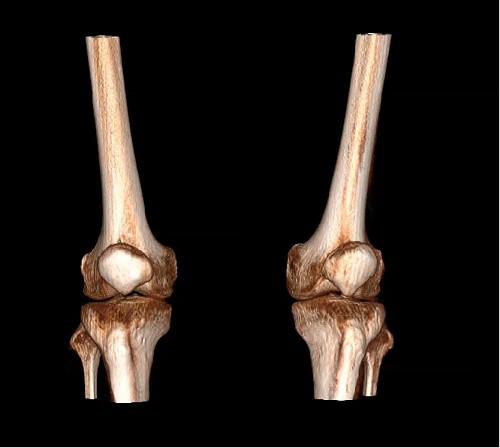

VR体绘制图像